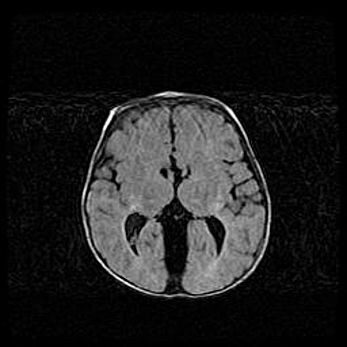

Сообщающаяся гидроцефалия. Кистозная энцефаломаляция головного мозга.

Возраст: 3 месяца 4 дня

Вес: 3100 г

Пол: женский

Окружность головы: 34 см

Срок гестации: 31 неделя

Кистозная энцефаломаляция головного мозга - одна из форм поражения головного мозга в детском возрасте. Характеризуется возникновением множественных и распространённых кист в коре, белом веществе и подкорковых образованиях головного мозга у плодов, новорождённых и детей раннего возраста. Развитие кистозной энцефаломаляции связано с внутриутробной асфиксией и гипотонией, родовой травмой, тромбозом синусов, пороками развития сосудов, инфекциями, сепсисом и другими причинами. Наиболее значимые инфекционные агенты: вирусы простого герпеса, цитомегалии, краснухи, токсоплазмы, энтеробактерии, золотистый стафилококк и другие.